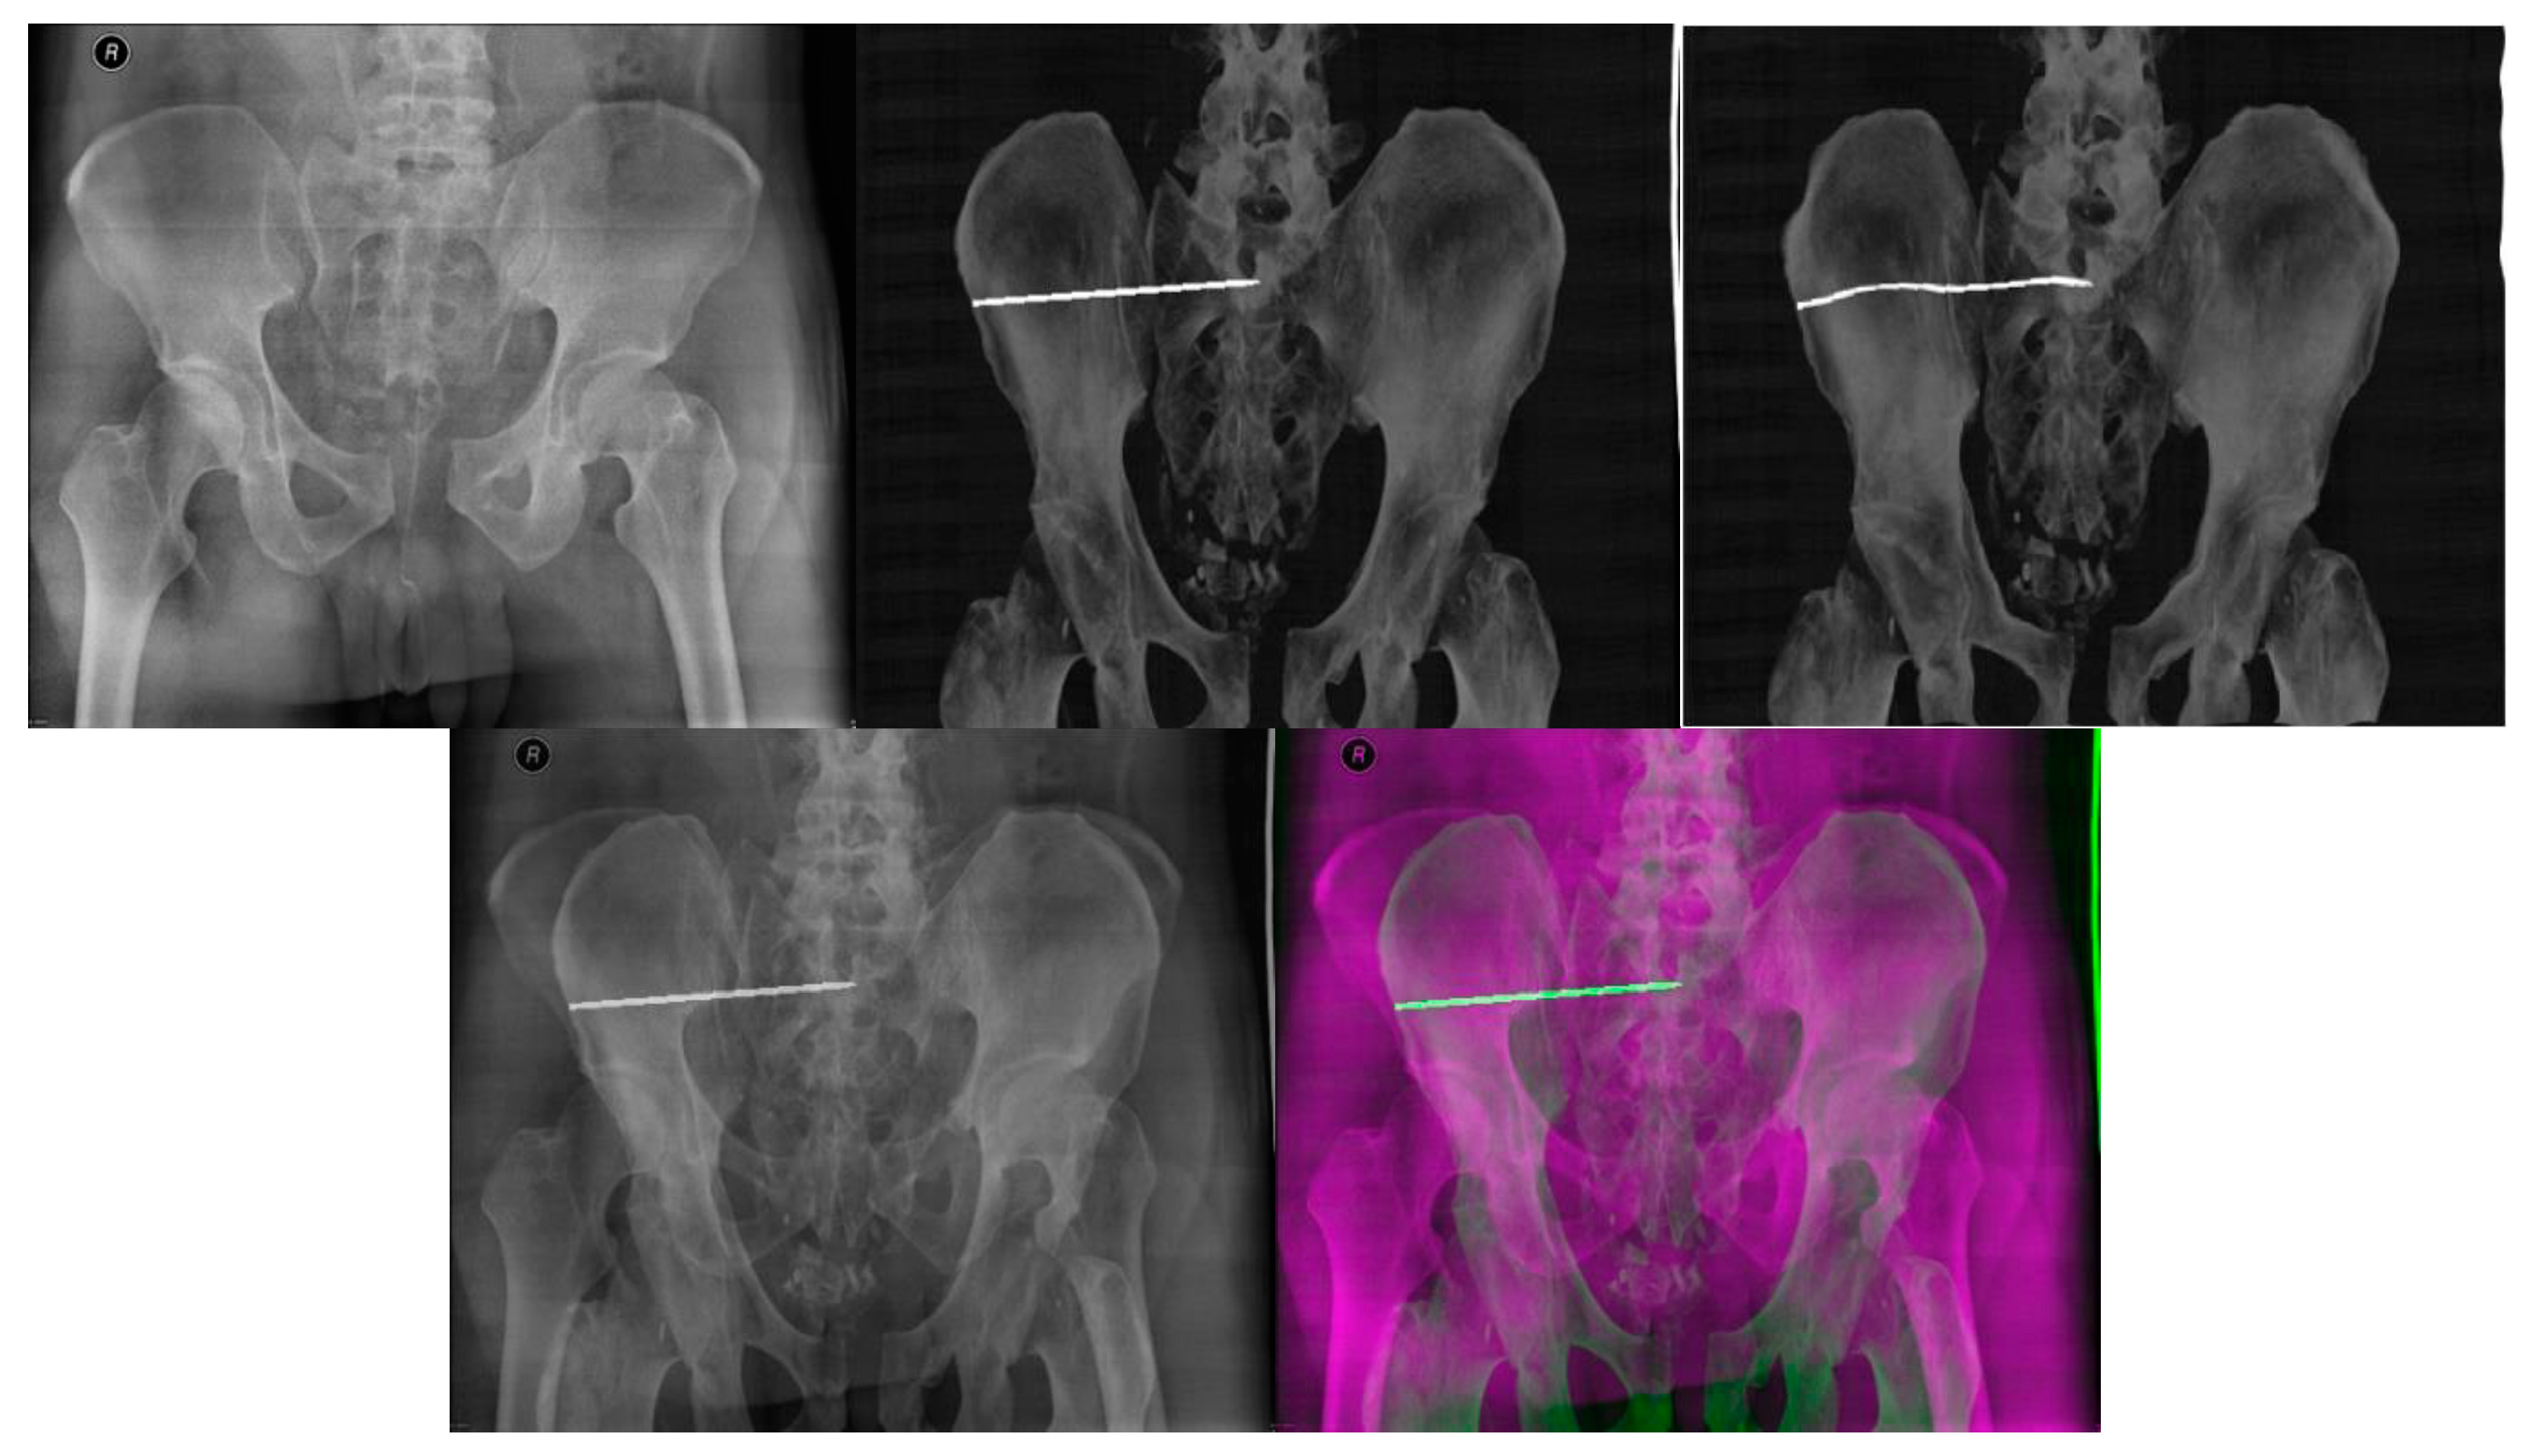

- Multimodal image registration of DRR projections to a reference X-ray image

- Multimodal (X-ray/CT) image registration for optimal CT slice selection according to the reference X-ray image.

| Patient 1 | 0.42 | 0.26 | 7.87 | 2° | 0.51 | 0.42 | 8.17 | 15° |

| Patient 2 | 0.50 | 0.36 | 9.86 | 0° | 0.40 | 0.42 | 9.68 | 345° |